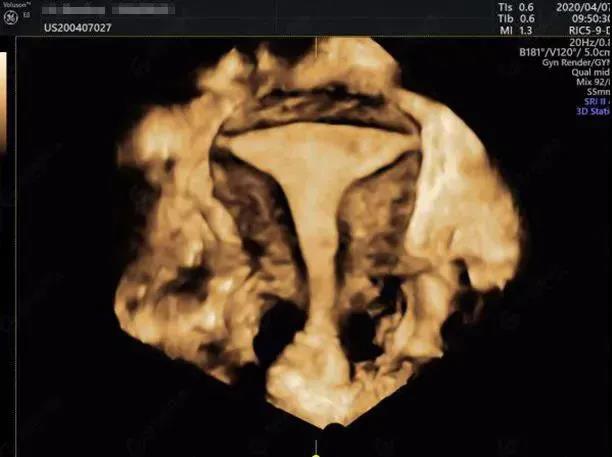

引起女性不孕因素主要有输卵管因素、盆腔因素、卵巢因素、免疫因素、精神因素以及子宫因素等,输卵管因素是女性不孕症的较常见的原因,输卵管阻塞、通而不畅或输卵管功能不良造成的不孕约占25~35%,因此输卵管通畅度检验是女性不孕检查的重要步骤。

1.了解输卵管通畅程度及其形态、阻塞部位;

2.了解宫腔形态,明确有无子宫畸形及类型,有无宫腔粘连、子宫黏膜下肌瘤、子宫内膜息肉及异物等;

长沙江湾妇产医院超声影像科团队运用GE-E10四维彩超,根据临床需求为患者制定个性化超声方案,可对包括子宫、输卵管、卵巢在内的女性生殖系统或盆腔相关的常见不孕原因进行系统性精准筛查,找出病因,对症治疗,并将其安全、无创、精准、便捷、经济的特点发挥到极致!